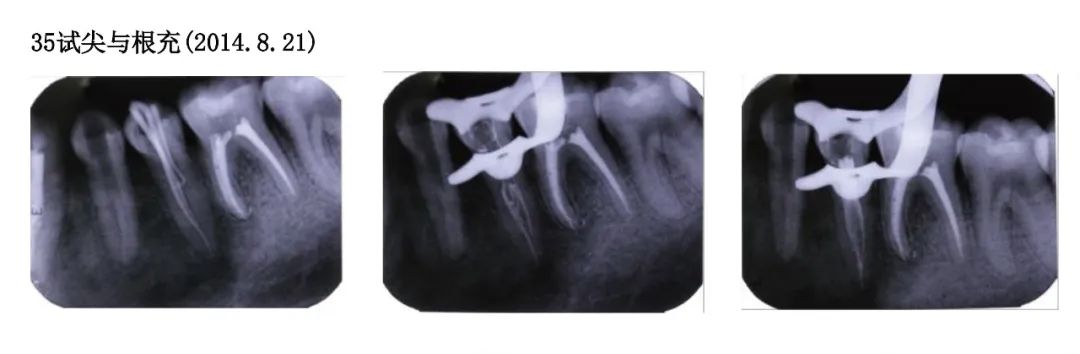

Trial apex and root filling for tooth 35 (2014.8.21)

Direct filling of composite resin for teeth 34 and 35 (2014.8.21)

Occlusal adjustment, polishing for teeth 34 and 35 (2014.8.21)